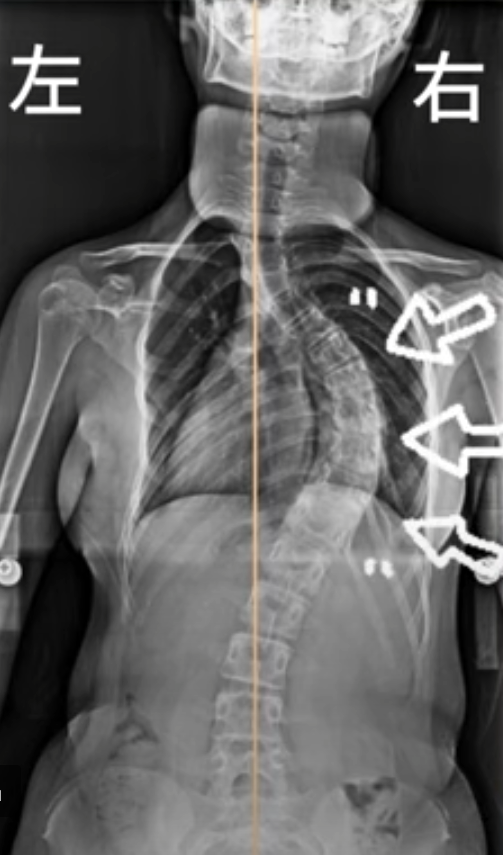

以胸椎右側彎為例的日常坐姿擺位